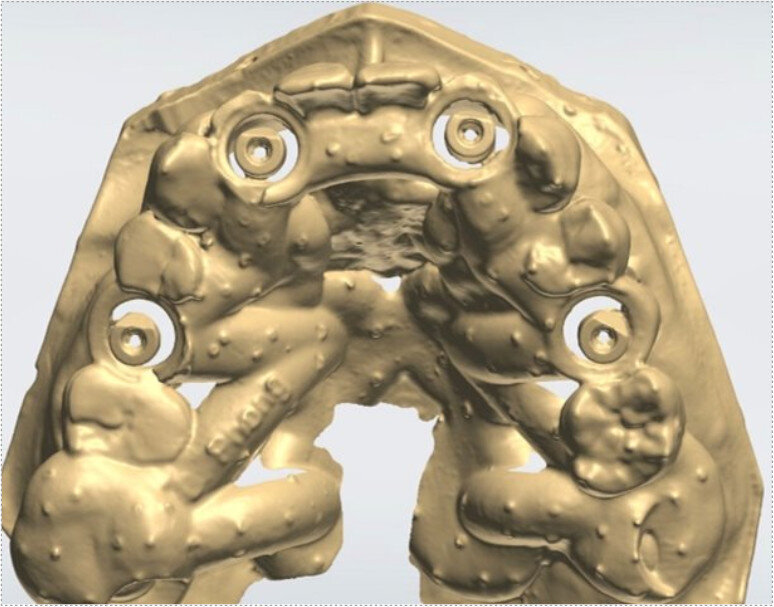

An intra-oral scan was taken to record the patient’s current oral situation, and the resulting STL file and the DSD fil (2D smile design image) were used to create the future prosthetic design with software for the laboratory (Figs. 3–6). The 3D radiographic DICOM data and the prosthetic design project STL file were superimposed in coDiagnostiX (Figs. 7–9) The fixation pin guide, bone reduction guide, surgical guide and bite registration guide were designed with coDiagnostiX (Figs. 10–13) and produced using 3D printing technology.

To design the prosthesis digitally, we first selected the screw-retained abutment (SRA) angle and gingival height (Fig. 14) and then we created the patient model on which we could connect the BLX implants with the SRAs selected from the Straumann library (Fig. 15). The implant placement guide was on the model, leveraging the high stability that we could gain from palatal support (Figs. 16 & 17). After printing the model, the BL  implant analogues were positioned using the template for navigation. The digital planning using coDiagnostiX (Version 9.14) allowed the dental technician to identify all the necessary parameters related to implant position (Figs. 18–22). Emergence profiles were set-up on the model (Fig. 23). The model was scanned using scan bodies, and a CAD/CAM temporary restoration was designed and milled in a PMMA-based restorative material (Figs. 24–29).